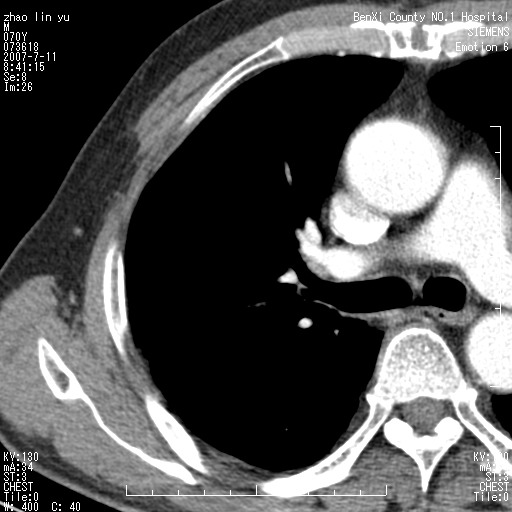

以下是引用王靖旗在2007-7-10 17:12:00的发言:[br] 男、70、咳嗽两个月,半年前换瓣手术,胸片未见异常,于昨天行x片发现右肺上野大片影,行ct扫描,这里是减薄图像,余肺正常。明天晚上会有增强扫描片,到时我会上传。[br][br] 冠状位请大家细看,应该是有意义的,[br][br] 请大家先看平扫发表意见。[br][br]

以下是引用zhangzhongshou在2007-7-10 21:43:00的发言:[br]右肺上叶周围型肺癌,以孤立型细支气管肺泡癌可能性大。